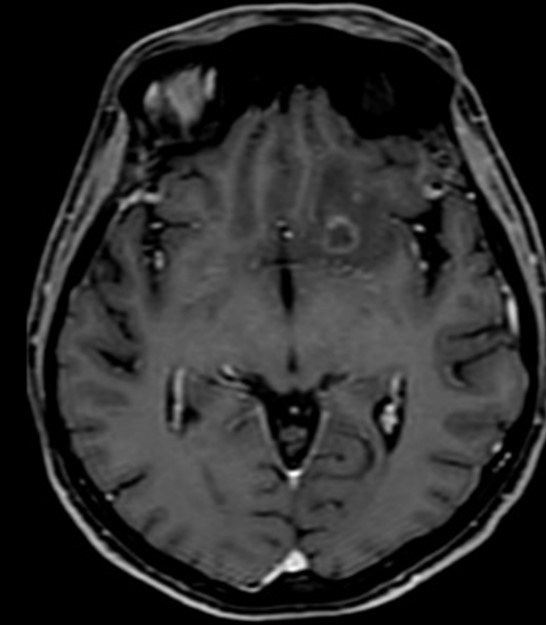

Result of MRI was at T1WI hypointense lesion as seen on (Figure 4), at fluid sensitive sequences T2WI \ FLAIR the lesion is hyperintense as shown in (Figure 5), after GAD enhancement there's irregular ring enhancement of the lesion (Figure 6). Followed by vasogenic edema that is visible in flair sequence at the medial aspect of base of frontal lobe that also affects the head of caudate nucleus. No diffusion restriction was seen in DWI and ADC sequences (Figure7a,7b). In SWI there's no detection of blood products.

Figure 4: Axial T1WI shows hypointense lesion at the LT frontal lobe.

Figure 5: Axial T2WI shows hyperintense lesion.

Figure 6: Axial T1+GAD shows irregular ring enhancing lesion.